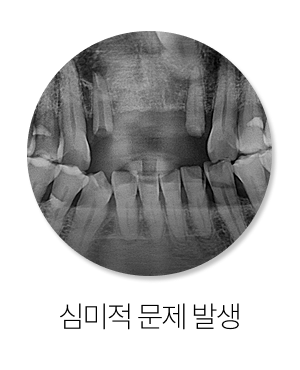

첫째, 빈 공간이 줄어들 수 있습니다.

임플란트를 계획할 때는 적절한 폭과 높이, 그리고 보철물이 들어갈 자리가 필요합니다.

그런데 인접치가 쓰러지고 이동하면 단순한 임플란트 치료가 더 까다로워질 수 있습니다.